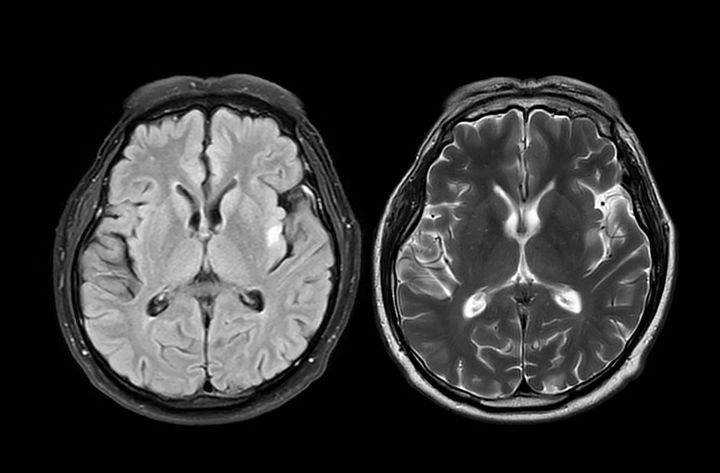

脳のMRI画像

※写真はイメージです